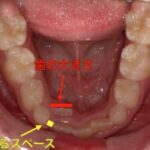

また上下の歯並びのアーチも大きく半円状に広がってきており、永久歯の生えるスペースを作り出すように移動しています。

右上の2番目の永久歯や右下の3番目の犬歯の生えるスペースがまだ足りていないので今後も継続して治療を行っていく予定です。